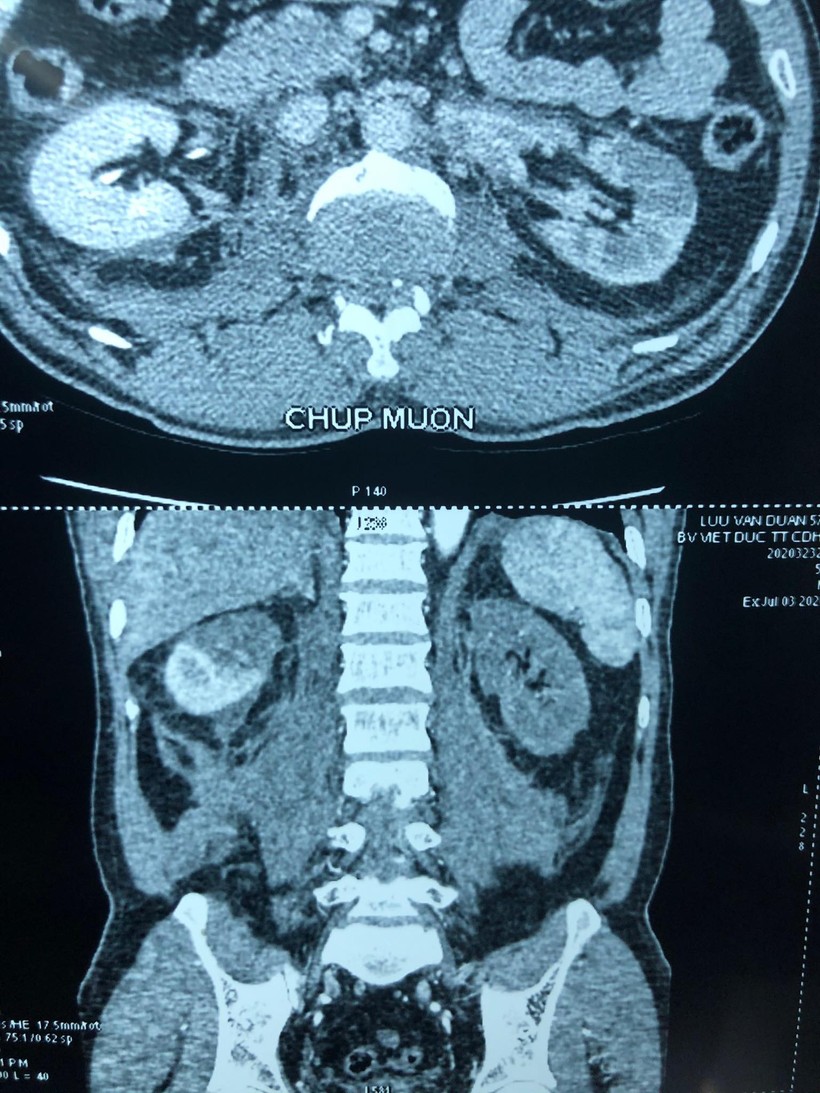

Với kết quả chụp chiếu tại bệnh viện, các bác sĩ phát hiện thận bên phải của nạn nhân có một huyết khối động mạch cực trên khiến phần cấp máu cho cực trên bị mất, thận bên trái thiếu máu hoàn toàn, chức năng thận giảm, có biểu hiện suy thận.